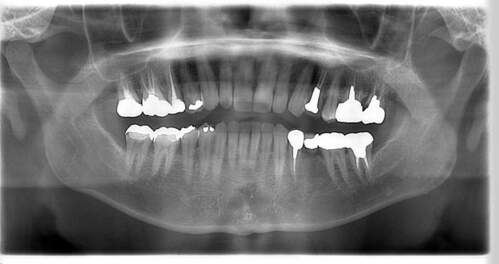

インプラント治療の症例1

レントゲン写真

- 透過像

| 年齢 | 50代・男性 |

|---|---|

| 主訴 | 右下歯が疼く |

| 治療内容 | ・右下6番インプラント ※1:FGG(遊離歯肉移植術)とは、足りない歯ぐきを上顎から上皮を切り取り移植する外科手術 |

| 治療費 | 合計:902,000円(税込) ■内訳 |

| 治療期間 | 9ヵ月 |

| 治療方針 | 右下の当該歯は歯根破折により保存不可能と診断しました。歯周疾患も伴っていたため抜歯後に骨吸収※1が大きく起こることが予測できました。チタンメッシュ併用骨再生誘導法(GBR※2)を選択しインプラント埋入と同時に行い自然な歯槽骨のラインを再現しました。またGBRを行う際にインプラント辺縁の付着歯肉の減少が起こる為、遊離歯肉移植術(FGG※3)を行い清掃性を考慮した形態に仕上げました。 ■治療方針の解説 治療した右下の歯をレントゲンで撮影したところ根本の部分に黒く写る箇所があり「根尖性慢性周囲炎※1」と診断。また歯周病も進行していました。 ※1 骨吸収・・・歯槽骨という歯を支える骨がなくなっていくこと |

| 担当者所見 | 主訴の右下だけでなく歯茎の腫れ、発赤があり不良補綴や不良充填など他にも治療箇所が多数ありました。プラークコントロールが不良であった為まずはブラッシング指導を行いセルフケアの重要性を理解していただくところからスタートしました。 右下6番の歯はインプラント治療を行なった結果審美的にも機能的にも患者様の満足を得ることができました。骨造成と歯肉移植も行なった為インプラントを支える十分な歯周組織の獲得ができたと思っております。 |